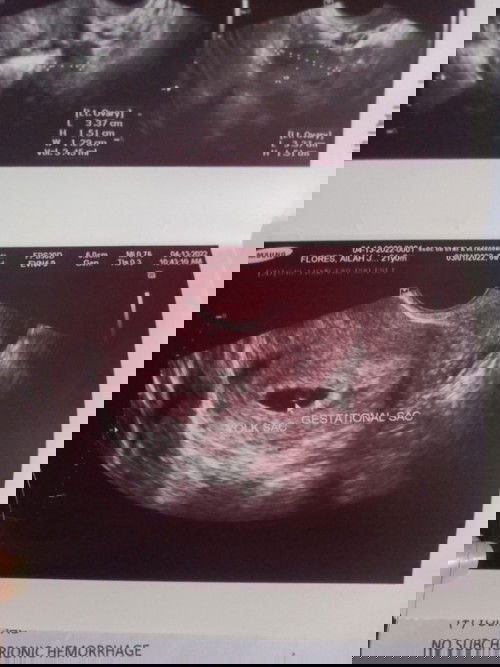

6weeks pregnant sac palang nakita. UPDATE! MAY BABY NAPO AND HEARTBEAT 10WEEKS PREGGY HERE

Hello mommies? Nagpa transv po ako kanina sad to say yolk and gestational sac lang po nakita. Normal po ba yun? Pinapabalik ako after 2weeks. Possible pa kaya magka embryo? Sobrang worried po ako. Sino napo nakaranas neto? Share naman po ng experience niyo. Nagbrown discharge dn ako nung isng araw e.#1stimemom#advicepls #worryingmom